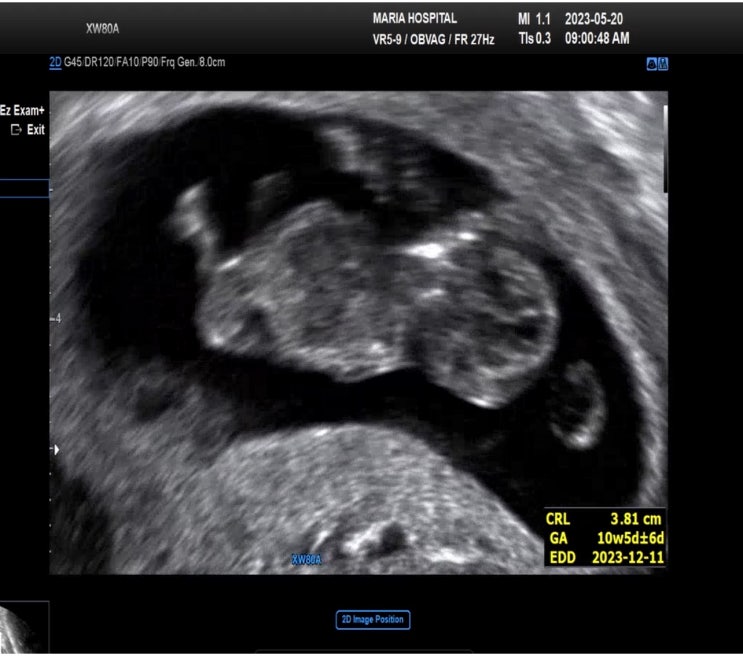

시험관 2차 성공 후 임신초기 4주 ~ 10주 기록

안녕하세요 오랜만이에요 ~ 서울마리아병원에서 시험관 2차 성공 후 임신 초기 기록 ! 부지런하지 않은 나...